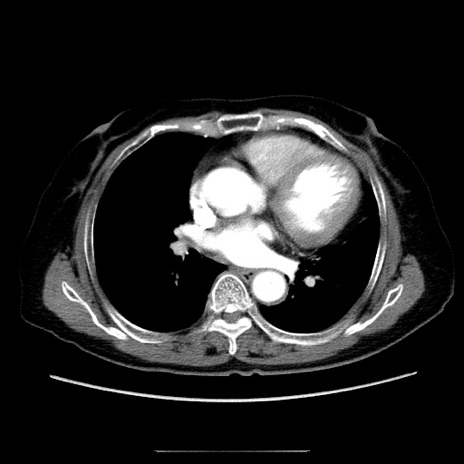

症例5(横断像)

【症例】70歳代女性

【主訴】お腹が張る

【現病歴】1週間くらい前から腹部膨満の自覚あり。昨日夜から増悪したため、本日救急外来受診。

【身体所見】意識清明、BT 36.5℃、BP 165/106mmHg、HR 80bpm、SpO2 98%、腹部:膨満、軟、自発痛・圧痛なし、触診にて不快感あり、腸蠕動音:減弱

【データ】WBC 12600、CRP 1.04